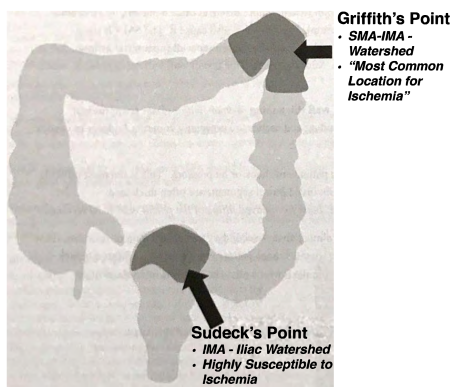

Segments à Risque ++

- Colites Ischémiques via les points de Griffits (angle splénique, AMS - AMI) et le point de Sudeck (jonction rectosigmoidienne, AMI - Iliaque)

ischemique Isechémique ischémique Griffith Sudeck water shed territories grifith sudek mesentérique mésenterique mésentérique mesenterique mesentere mésentere mesentère mesentére mésentére mésentère colite colitis ischemique ischémique